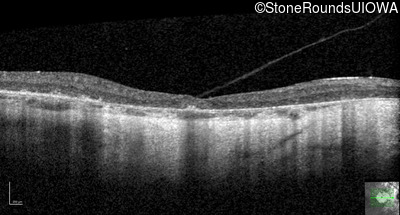

Optical Coherence Tomography - Left - 20/20 -1

Exemplar / OCT Stack